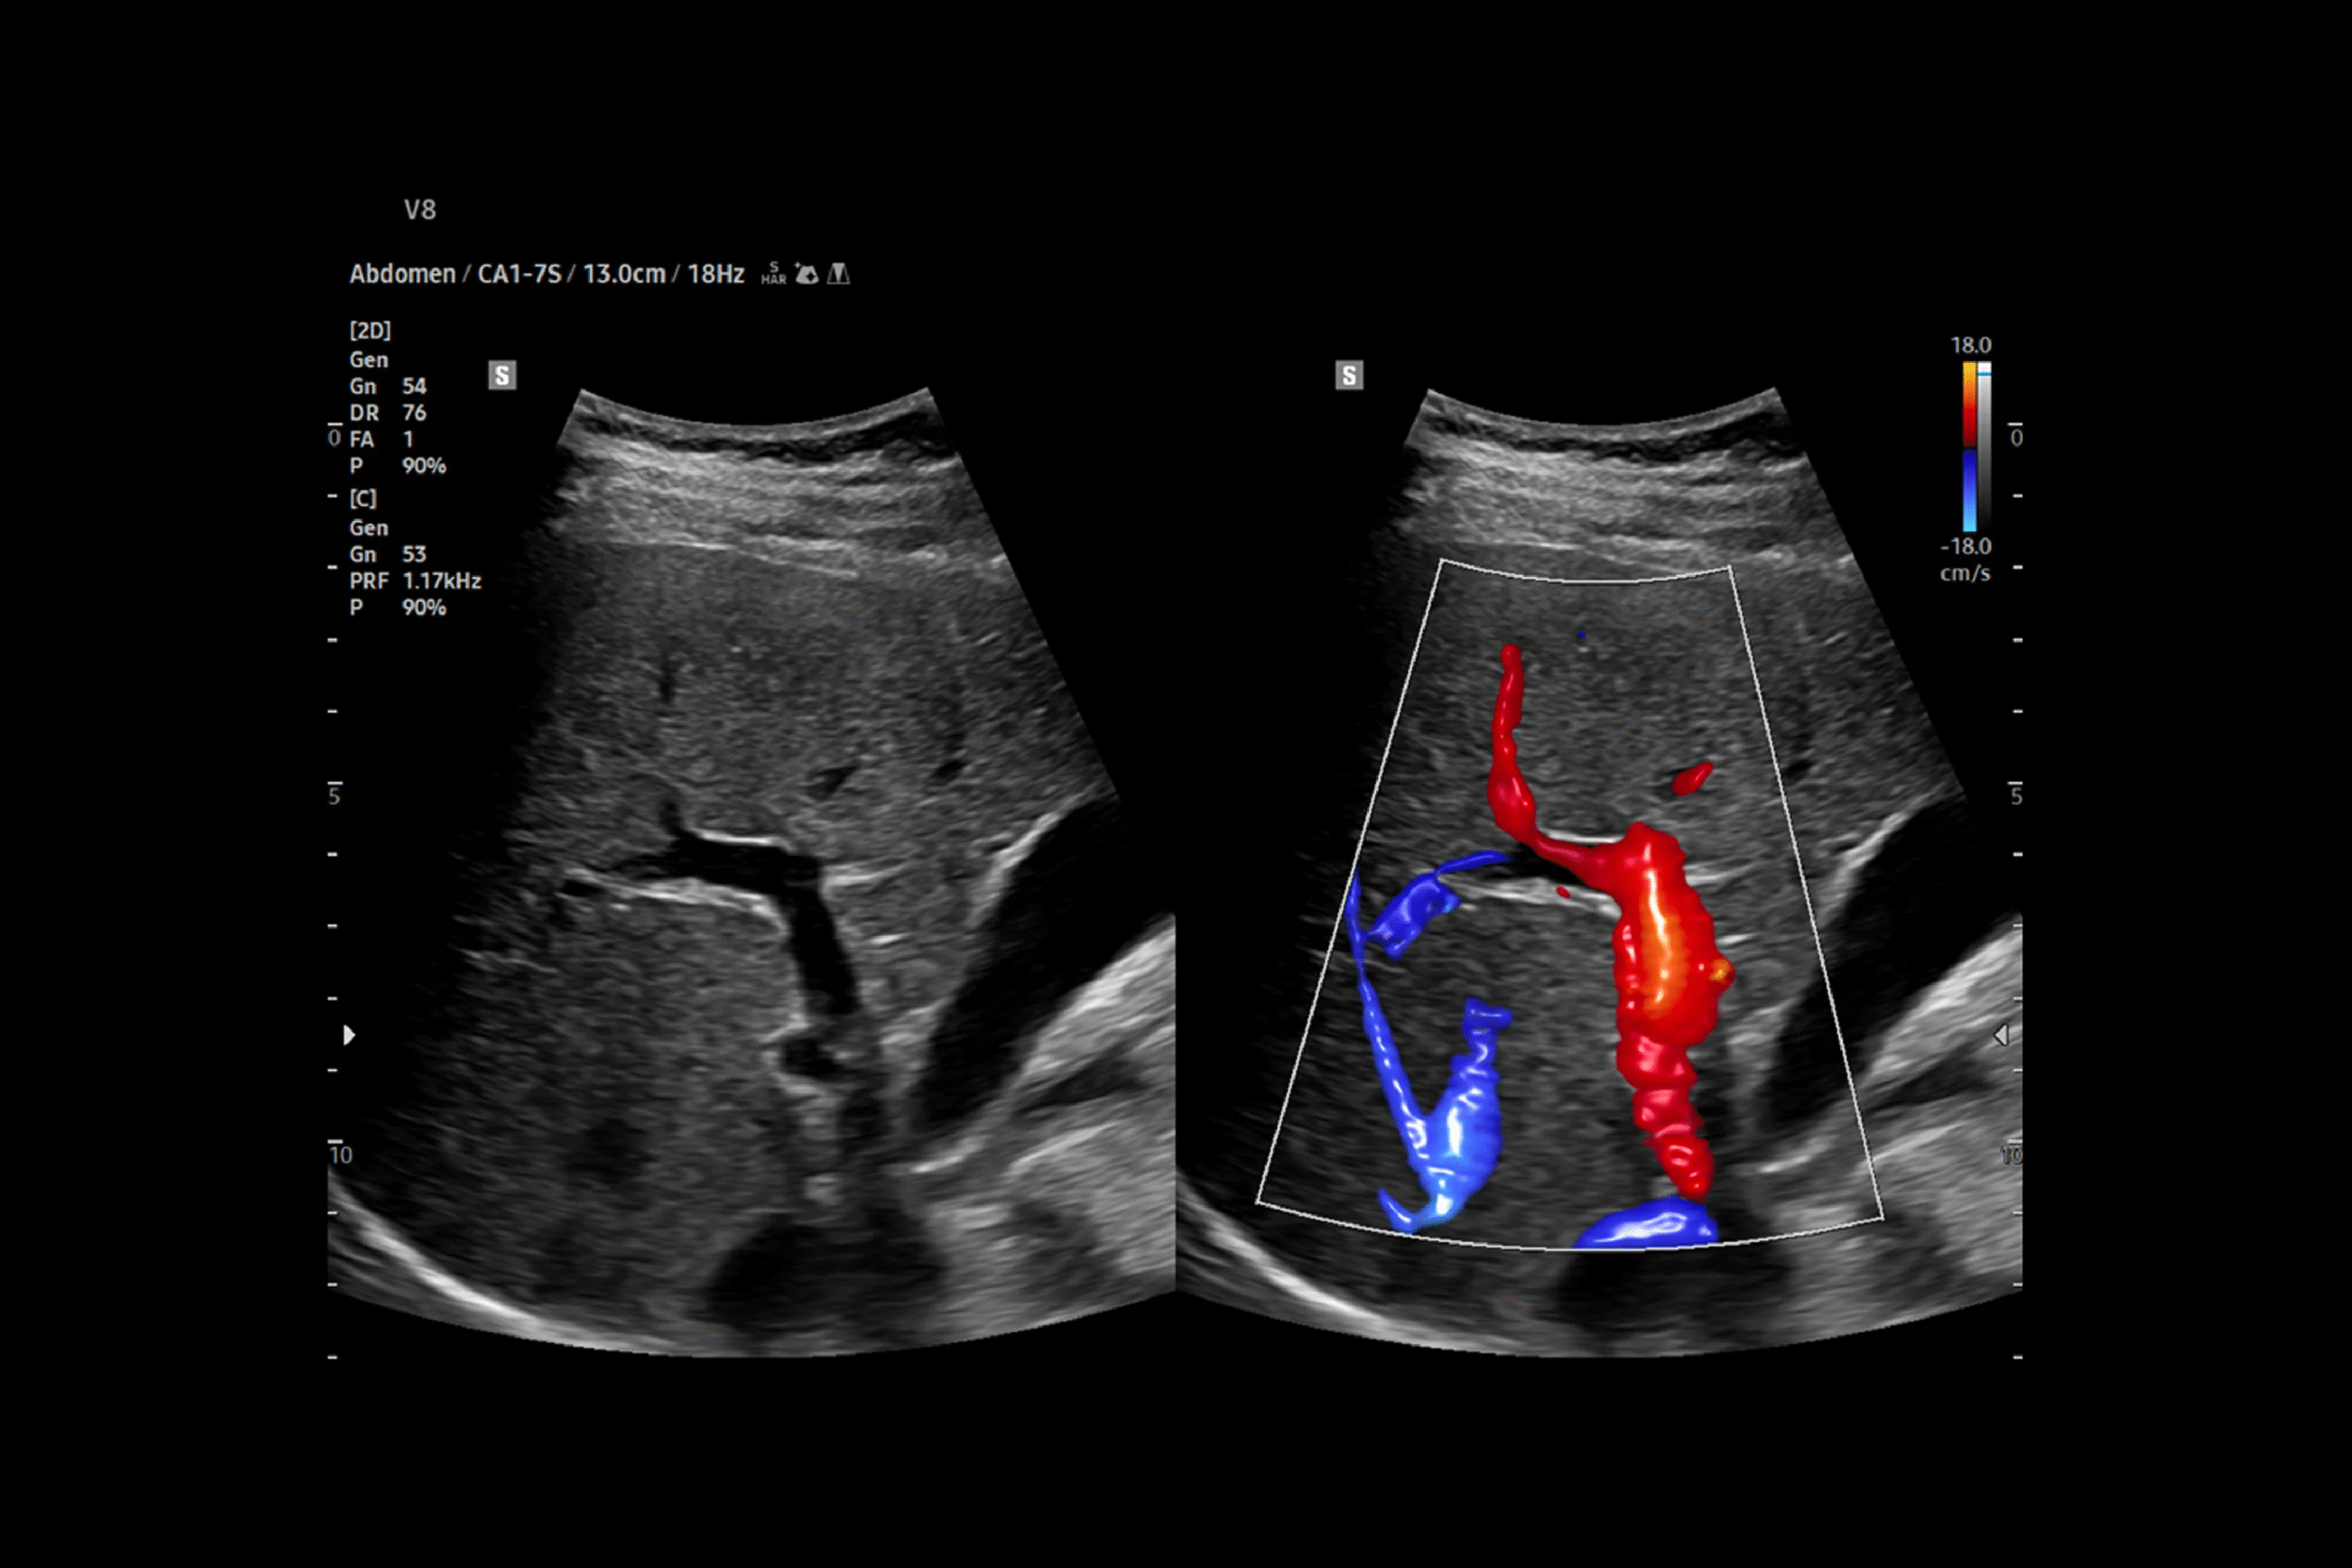

Colour Doppler

Ultrasound in Borivali

Colour Doppler Ultrasound is a specialized imaging technique that visualizes blood flow in real-time, helping doctors assess circulation in arteries and veins with exceptional clarity. At Narayana Imaging, we use state-of-the-art Doppler equipment to detect blockages, clots, and vascular abnormalities, as well as to evaluate organ perfusion and fetal well-being.

Whether you need a vascular ultrasound, cardiac Doppler, or prenatal Doppler, our advanced imaging services are designed to support timely and accurate healthcare decisions.